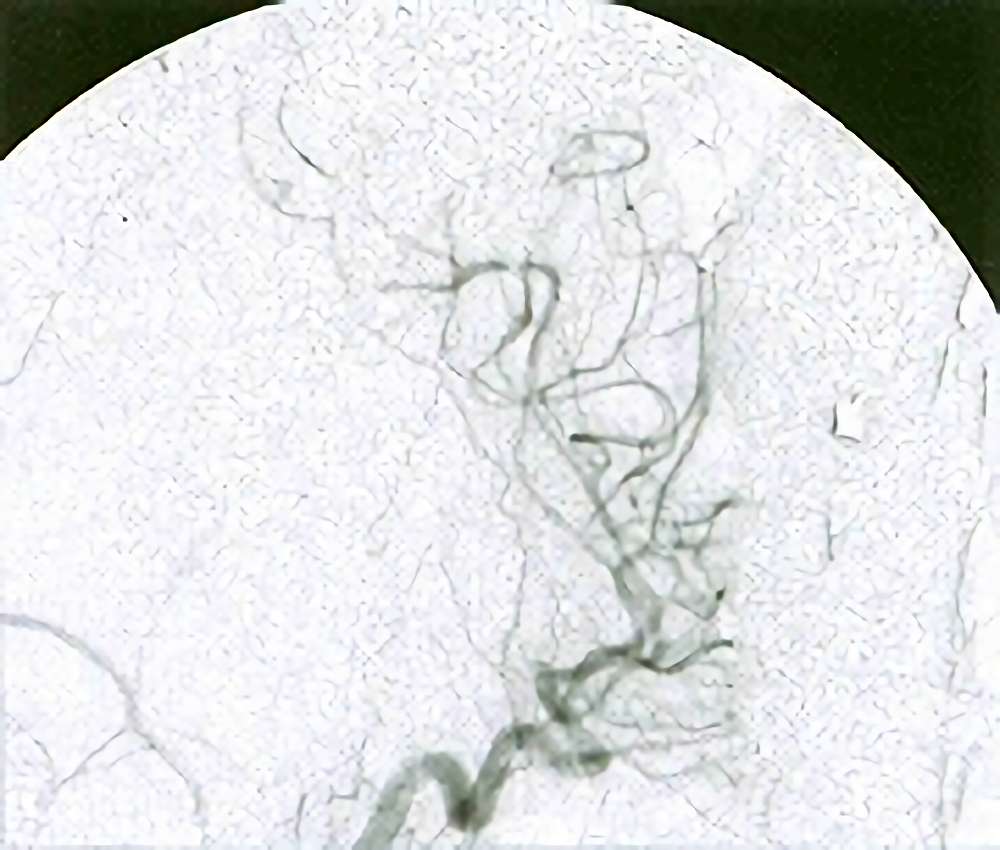

'19年5月

30代

富永/久貝

右中小脳脚 出血再発

SM 3(S1,E1,V1)

米国の病院

No.359 モニタリング

No.359 手術前

No.359 手術中

No.359 手術後

出血既往があり。2回の手術前血管内手術の後に、

Lateral transpeduncular approachにより再々出血予防を目的に

摘出手術を行う。完全摘出であることを確認した。

手術による合併症や後遺症なしで退院した。経過良好。